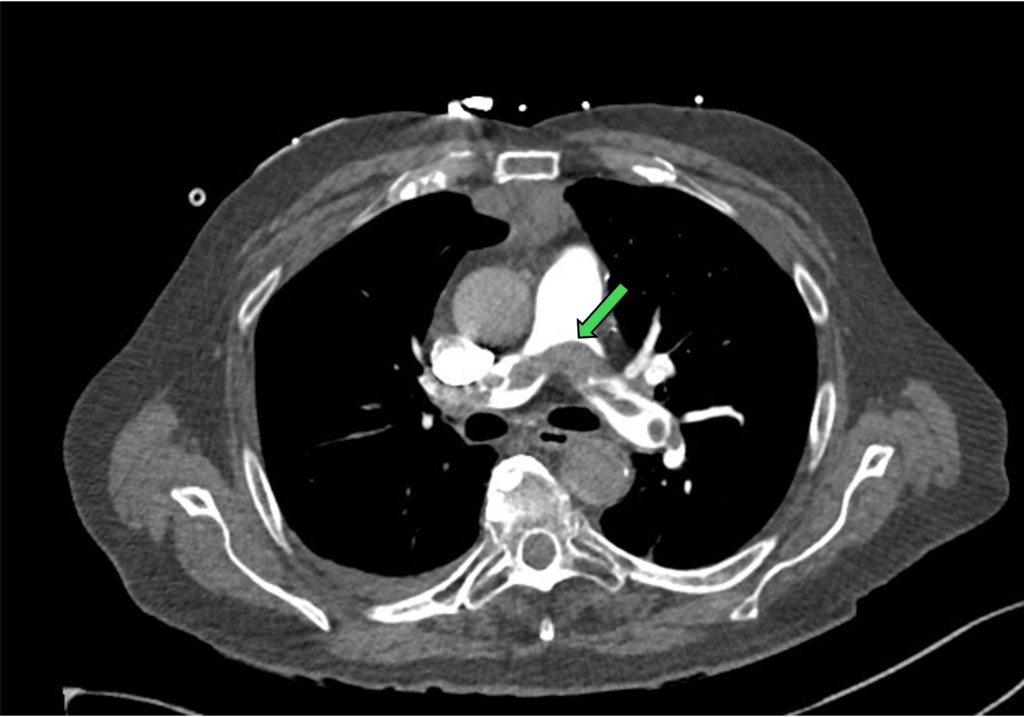

We should start from the pulmonary trunk (use axial view) and browse through each of the segment and sub-segment branches to look for filling defect. This is the low attenuation area within the contrast-enhanced lumen.

Figure 3: pulmonary trunk (green arrow) with bifurcation to left and right main PA

In this situation, it does help to be familiar with the PA anatomy and its branches. Below is the crude schematic diagram of the main PA and its branches.